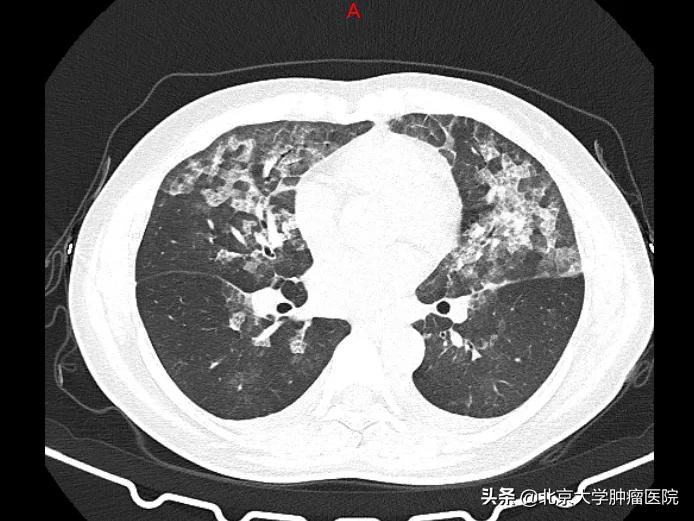

两女子肺部CT全是白色 不是新冠肺炎竟是消毒过度

近日,张女士和王女士患了同一种病,均因头晕、乏力到医院就诊,虽然没有出现发烧及咳嗽、呼吸困难等症状,但两人的肺部CT均呈毛玻璃影,难道是新冠肺炎?

原来,两位女士居家期间,因为害怕患上新冠肺炎,每天定时在家里喷洒高浓度的84消毒液。消毒液会对我们的肺造成怎样的伤害?